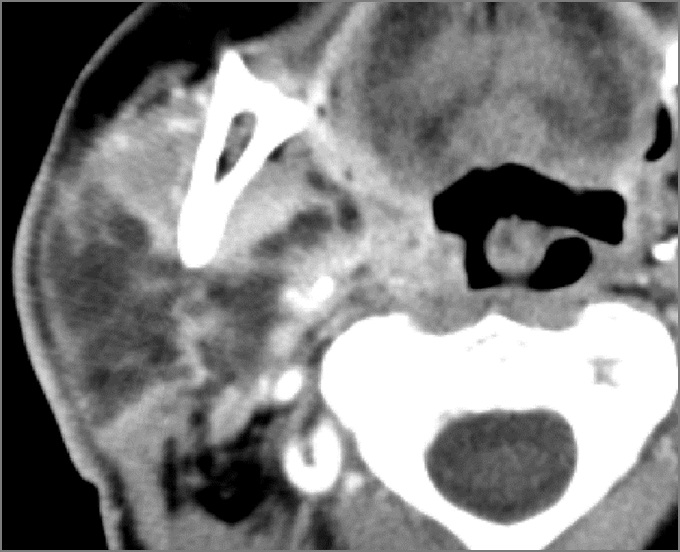

Oral Cavity, Floor of the Mouth, Maxilla and Mandible

There is excessive enhancement or thickening of the fat or other soft tissues within or surrounding the buccal space, masticator space, floor of the mouth, submandibular space or the adjacent superficial fascia or subcutaneous fat and skin. [Yes/No]

There is subperiosteal abscess or an abscess cavity adjacent to or involving the maxilla or mandible. [Yes/No]

There is endodontal or periodontal disease that might be causing cellulitis or abscess. [Yes/No]

The lingual or buccal aspect of the maxilla is eroded. [Yes/No]

The lingual or buccal aspect of the mandible is eroded. [Yes/No]